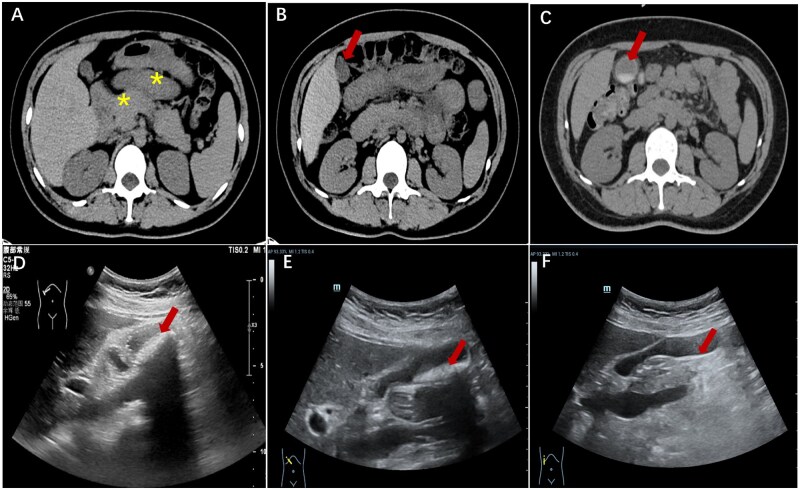

Ceftriaxone-induced pseudocholithiasis with acute cholecystitis in a puerperal woman: a case report.

头孢曲松诱发的假性胆结石合并急性胆囊炎1例。